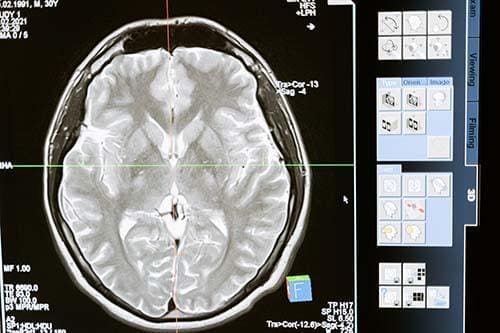

Transformative Potential of Hyperbaric Oxygen Therapy for Traumatic Brain Injury

As the brain’s most sought-after resource, oxygen fuels its ceaseless activity. Even though only a fraction of the brain’s capacity is active at any given time, nearly all the oxygen delivered is harnessed. This oxygen nourishes different brain regions, adapting as needed to perform tasks, particularly during multitasking endeavors. Innovative technology, such as functional magnetic resonance tomography (fMRI), unveils these shifts in blood perfusion that accompany varying tasks.